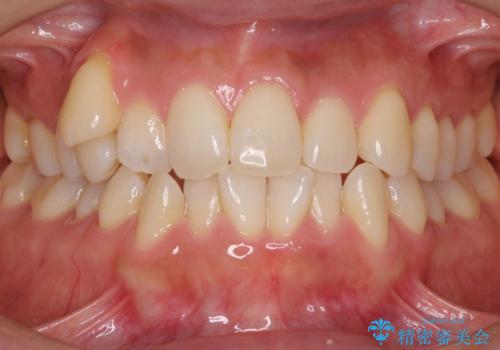

八重歯 上下の正中のずれ 40代で抜歯矯正

- 八重歯と上下の正中のずれを気にして来院。

上の前歯の正中が右にずれていました。

小臼歯抜歯を行い、ワイヤー矯正を行いました。